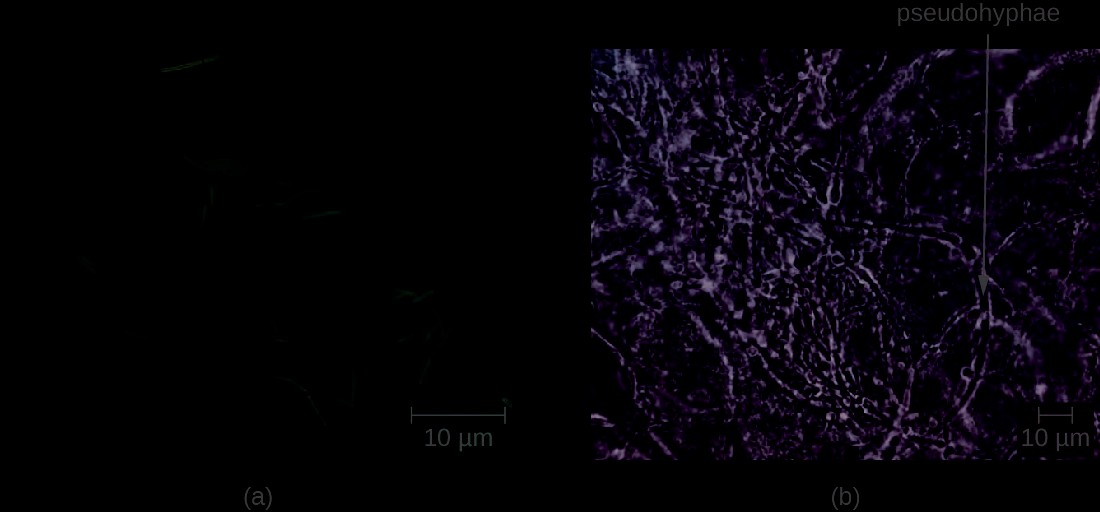

Diagnosis of vaginal candidiasis can be made using microscopic evaluation of vaginal secretions to determine whether there is an excess of Candida. Culturing approaches are less useful because Candida is part of the normal microbiota and will regularly appear. It is also easy to contaminate samples with Candida because it is so common, so care must be taken to handle clinical material appropriately. Samples can be refrigerated if there is a delay in handling. Candida is a dimorphic fungus, so it does not only exist in a yeast form; cultivation can be used to identify chlamydospores and pseudohyphae, which develop from germ tubes (Figure 23.22). The presence of the germ tube can be used in a diagnostic test in which cultured yeast cells are combined with rabbit serum and observed after a few hours for the presence of germ tubes. Molecular tests are also available if needed. The Affirm VPII Microbial Identification Test, for instance, tests simultaneously for the vaginal microbes C. albicans, G. vaginalis (see Bacterial Infections of the Urinary System), and Trichomonas vaginalis (see Protozoan Infections of the Urogenital System).

Figure 23.22 Candida can produce germ tubes, like the one in this micrograph, that develop into hyphae. (credit: modification of work by American Society for Microbiology)